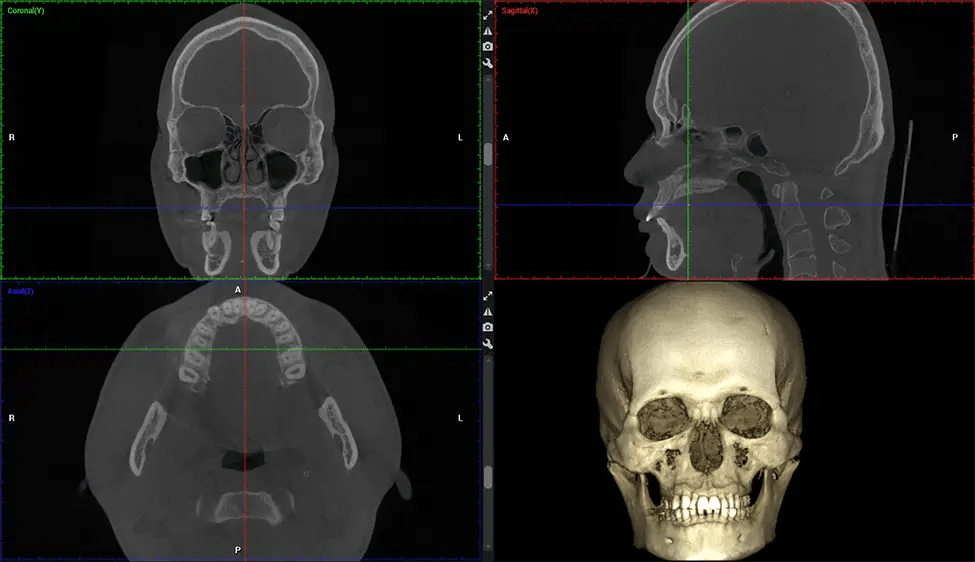

Existen muchos beneficios al utilizar la tecnología CBCT, especialmente en comparación con el formato tradicional de rayos X 2D. Una de las ventajas más importantes de las exploraciones CBCT es que proporcionan mucha más información que las radiografías tradicionales. Una exploración le permite a su dentista ver imágenes desde todos los ángulos de su mandíbula y boca, incluidos los senos nasales, la cavidad nasal, los pómulos y otras áreas circundantes. Esta información adicional ayuda a su dentista a elaborar un plan de tratamiento integral que aborde todos los aspectos de su salud bucal.

Después del proceso de escaneo, las imágenes de rayos X capturadas son procesadas por el software CBCT, que aplica algoritmos para reconstruir una imagen 3D detallada del área escaneada. El software recopila estas imágenes de rayos X individuales y crea una representación digital en 3D de la anatomía del paciente. El dentista o el radiólogo pueden ver y analizar la imagen CBCT 3D reconstruida. Esta imagen se puede manipular, rotar y acercar o alejar para examinar estructuras específicas y evaluar la condición del paciente.

Planmeca Viso G7 CBCT (Cone Beam CT Scan) está diseñado para superar las demandas de los líderes de la industria, los especialistas y las grandes instituciones. Tiene un gran sensor de ø25×30 cm con cuatro cámaras integradas. Puede capturar tamaños de volumen ilimitados, desde ø3×3 cm hasta ø30x30cm, capturando el casquete escutelario a través de C7 en la columna cervical. Planmeca Viso G7 ofrece el escaneo de volumen único más grande de la industria de ø30×19 cm. Está preparado para manejar modalidades de imágenes avanzadas como la tecnología Planmeca ProFace® y Planmeca 4D™ Jaw Motion. El soporte occipital para la cabeza permite una visión sin obstáculos del tejido facial.